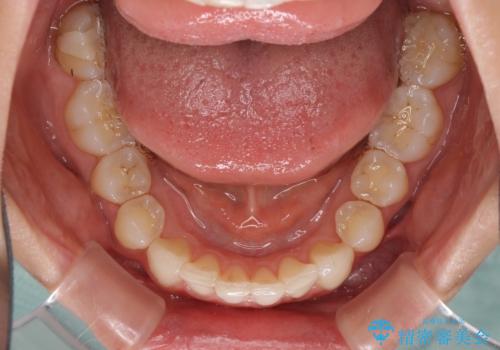

上顎前歯が2本欠損 インビザラインによる叢生の解消

- 深い咬み合わせと前歯のデコボコを気にして来院された患者様です。

上顎前歯2本が欠損しているため、妥協的なゴールを設定しインビザラインで矯正治療を行うこととしました。

上下前歯の大きさのアンバランスにより、深い咬み合わせと奥歯の咬みにくさがなかなか解決されず、治療に長期間を要することとなりました。